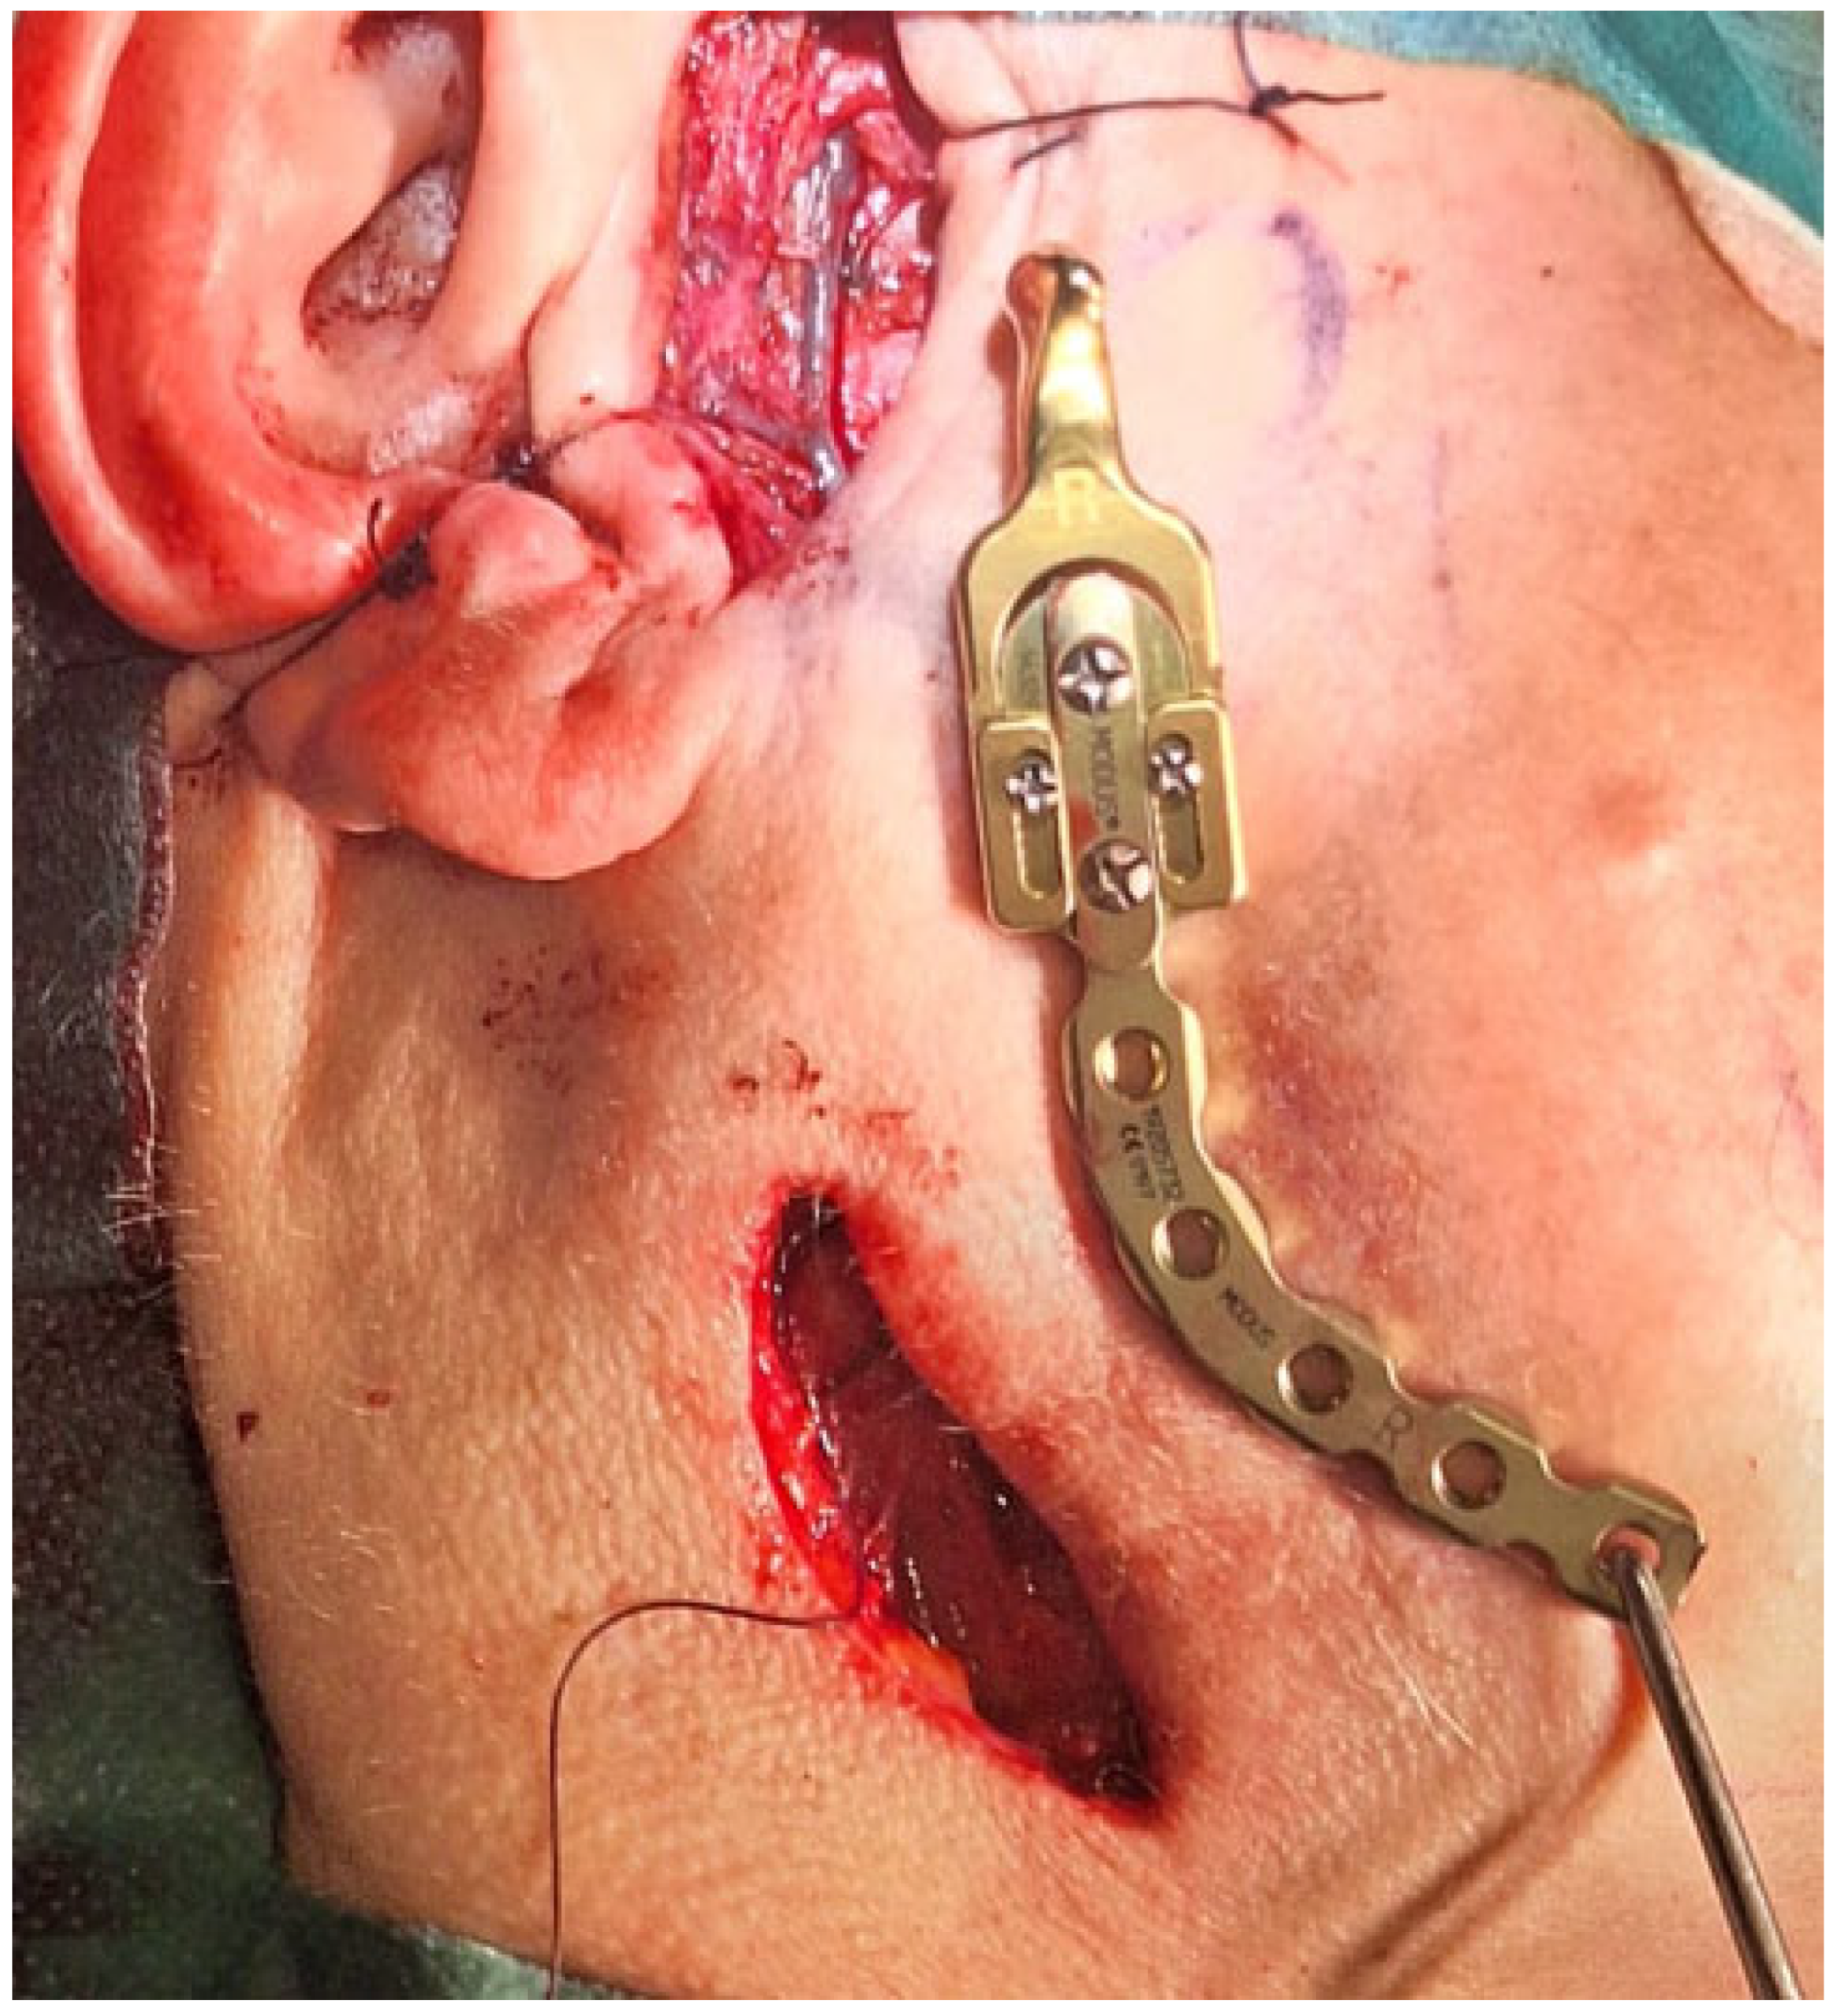

Figure 4. The surgical double approach consisted of the preauricular approach and the submandibular approach. The nasotracheal tube was sutured to the nasal septum and then retruded distally as per the tube placement algorithm [6]. A layer-by-layer preparation granted a good surgical view of the operated field with good protection of the facial nerve fibres. The TMJ standard prosthesis used was the Medartis 2.0 Modus System (Basel, Switzerland—right condylar head prosthesis (Titanium ASTM F67) with a carrier element, 2.0 mm four connecting screws screwed together with Medartis Reco plate 2.5, 2.5 mm connecting screws for proper mandibular vertical ramus height reconstruction, a stable position on the healthy part of the right mandibular ramus, and an angle free of OKC lesion. The pterygoid muscles were healthy and were sutured back to their initial position, in this case towards the titanium condylar head. The main lesion was located in the mandibular bone and had some cortical spread in the joint area. The articular disc and part of the capsule were healthy and not involved in the lesion, and because of that, fat grafting was not necessary. Any additional iliac crest bone grafting or fat was also not necessary. An additional four IMF (intermaxillary fixation) screws (Medartis, Basel, Switzerland), 2.0 system speed-tip 8/11 mm long, were used with elastic fixation. During the postoperative period, the patient was scheduled to use elastic rubbers on the IMF screws to stabilize the occlusion and surgery results. Currently, a custom-made individual TMJ prosthesis seems to be a good gold standard of treatment, especially in cases involving condylar disc damage, disruptions along the condylar fossa, and total joint resection. In some cases, such an approach with a standard, not custom patient-made, individual TMJ endoprosthesis solution is also quite effective, with fewer costs, good functional results, easy placement, no need for further glenoid fossa preparation, and the presence of just one metal alloy, the titanium. In this instance, the overall surgery outcome was very good, and the patient was satisfied with the results and the decreased necessity for any more advanced and costly procedures.